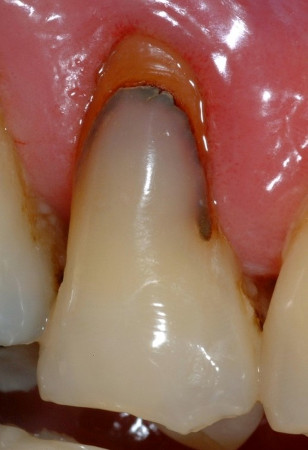

Fig. 2 : Malgré leurs excellentes propriétés, la mise en place des résines composites est techniquement plus exigeante (Avec l’aimable autorisation du Pr B. Van Meerbeek, université catholique (KU) de Louvain – BIOMAT, Belgique).plus influents).

3. matériaux combinant les propriétés des deux classes de matériaux précédentes, tels que les verres ionomères modifiés par adjonction de résine. Les résines composites microhybrides et nanohybrides sont dotées d’excellentes propriétés physiques, notamment d’une grande résistance à l’abrasion et à l’érosion, d’une résistance élevée à la flexion, d’une bonne aptitude au polissage, et de qualités esthétiques. De plus, ces matériaux peuvent être mis en place par une technique adhésive qui permet des traitements dentaires minimalement invasifs. La mise en place des résines composites nécessite notamment un contrôle très strict de l’humidité– dont l’obtention est généralement difficile en cas de caries radiculaires – et exige un processus en plusieurs étapes comme un mordançage à l’acide et l’application de produits adhésifs. Ces dernières années, les fabricants se sont efforcés de simplifier ce processus, notamment en combinant les étapes de mordançage et d’application de l’adhésif, mais la mise en œuvre – en particulier dans les zones juxta-gingivales ou sous-gingivales – reste toutefois techniquement complexe (Fig. 2).

Alors que seules les dernières générations de ciments verres ionomères (CVI) sont de plus en plus utilisées pour restaurer les cavités soumises aux contraintes, cette classe de matériaux a toujours été une solution valable pour les lésions cervicales (car les problèmes liés à l’abrasion et aux contraintes sont moins importants qu’au niveau des surfaces occlusales et proximales). Les verres ionomères modifiés par adjonction de résine ont tout particulièrement montré un taux de survie élevé dans les lésions cervicales (il convient toutefois de noter que de nombreuses études les évaluaient dans des lésions non carieuses). La dernière génération de matériaux, dénommée verres hybrides (Fig. 3), se caractérise par une grande stabilité à l’abrasion et à l’érosion, et par une meilleure résistance à la flexion. Ces propriétés sont dues à des modifications de la composition chimique du matériau, principalement à l’ajout d’une phase vitreuse constituée de particules plus petites et de chaînes d’acide acrylique plus longues.